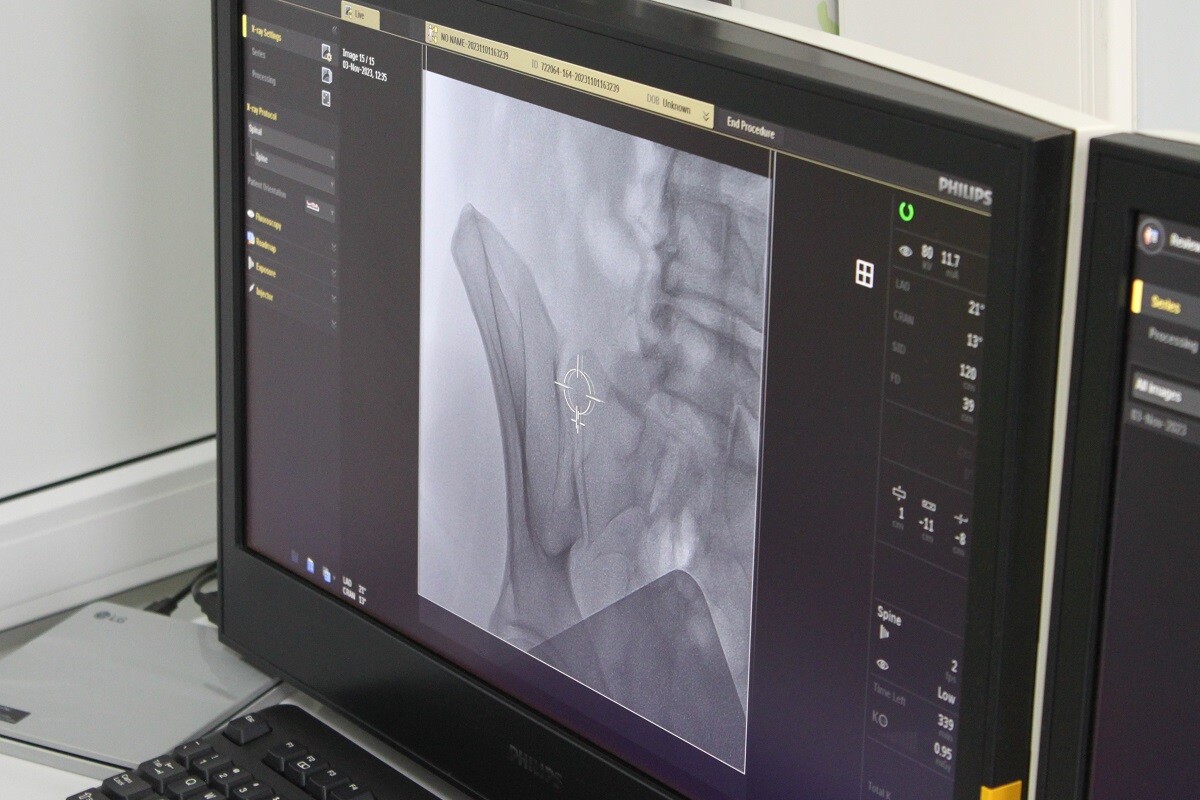

«Суть радиочастотной абляции заключается в том, что пациенту, который находится под местной анестезией, делается небольшой укол в проекцию нужного сустава. Врач оперирует, ориентируясь на рентген-экран, который в режиме реального времени показывает нужный сустав пациента, – поясняет Евгений Белевский. – С помощью специального тестового оборудования врач проверяет, не будут ли во время операции задеты двигательные нервы. Затем к нужному месту в суставе подводится электрод. Через него подается высокое интенсивное поле, которое разогревает ткань. В итоге точечного воздействия погибают маленькие нервы, отвечающие за болевую импульсацию. Моторно-двигательная функция пациента сохраняется в полном объеме. Время реабилитации минимально. Пациент уже вечером может возвращаться домой».

3 ноября были проведены три операции с помощью метода радиочастотной абляции: у пациентов с грыжей в поясничном отделе позвоночника, с артрозом крестово-подвздошного сочленения и фасеточных суставов. Их провел Евгений Белевский, которому ассистировал травматолог клиники.